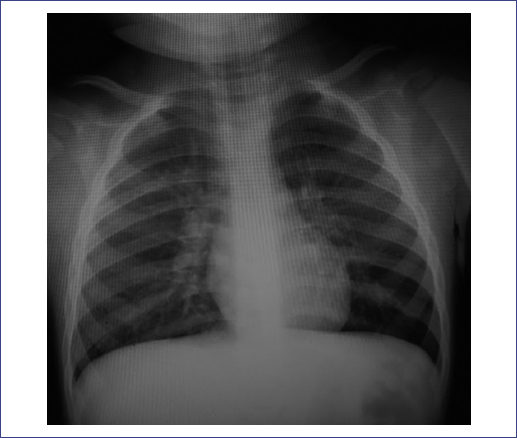

Initially, the patient was treated for an airway infection, managing respiratory distress with salbutamol and ipratropium bromide. Due to the lymphadenopathies and fever, a chest X-ray was performed, which revealed pulmonary hyperinflation (Fig. 2).